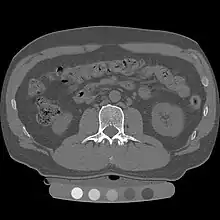

Quantitative computed tomography (QCT) is a medical technique that measures bone mineral density (BMD) using a standard X-ray computed tomography (CT) scanner with a calibration standard to convert Hounsfield units (HU) of the CT image to bone mineral density values.[1] Quantitative CT scans are primarily used to evaluate bone mineral density at the lumbar spine and hip.

Originally, conventional 2D QCT used individual, thick CT slice images through each of multiple vertebrae which involved tilting the CT scanner gantry to align the slice with each vertebra. Today, modern 3D QCT uses the ability of CT scanners to rapidly acquire multiple slices to construct three-dimensional images of the human body. Using 3D imaging substantially reduced image acquisition time, improved reproducibility and enabled QCT bone density analysis of the hip.[1]

At the spine, QCT is used to measure the bone mineral density of only the spongy interior bone separately from the dense cortical bone that forms the exterior walls of the vertebrae.[4] The trabecular bone has much higher metabolic activity than the cortical bone and so is affected by age, disease and therapy-related changes earlier and to a greater degree than cortical bone. This means that QCT of the spine has an advantage compared to other bone density tests because earlier changes in bone mineral density may be detected .[1]

Clinically, QCT is used at the hip to produce areal BMD measurements and T-Scores that are equivalent to DXA measurements.[5] The exam can be done without particular attention to the positioning of the patient's limbs because the software allows the hip anatomy to be manipulated after the image is captured, allowing the exam to be performed on patients with arthritic hips who may find traditional exams uncomfortable.